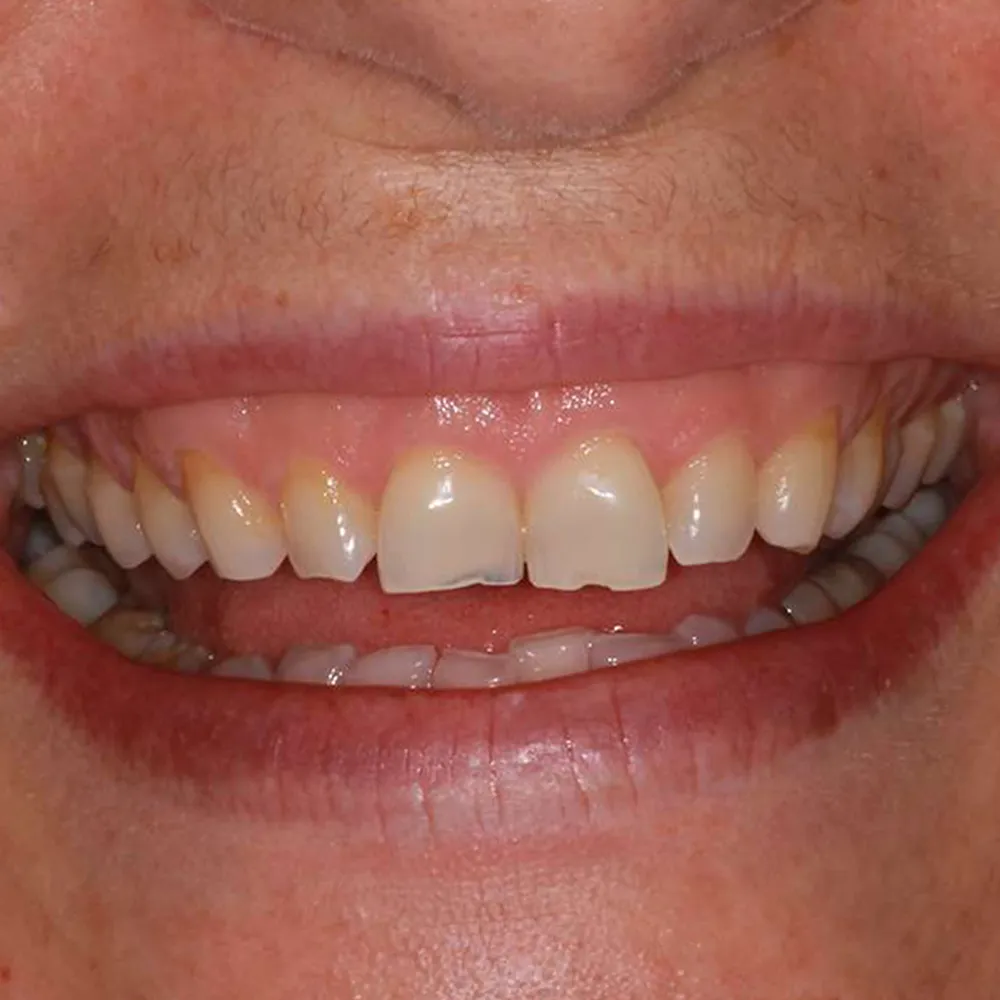

Real Stories, Real Results: Case Studies Showcasing How Our Personalized Approach Transforms Smiles and Lives

Complex Cases

Witness the Remarkable Changes We Can Achieve